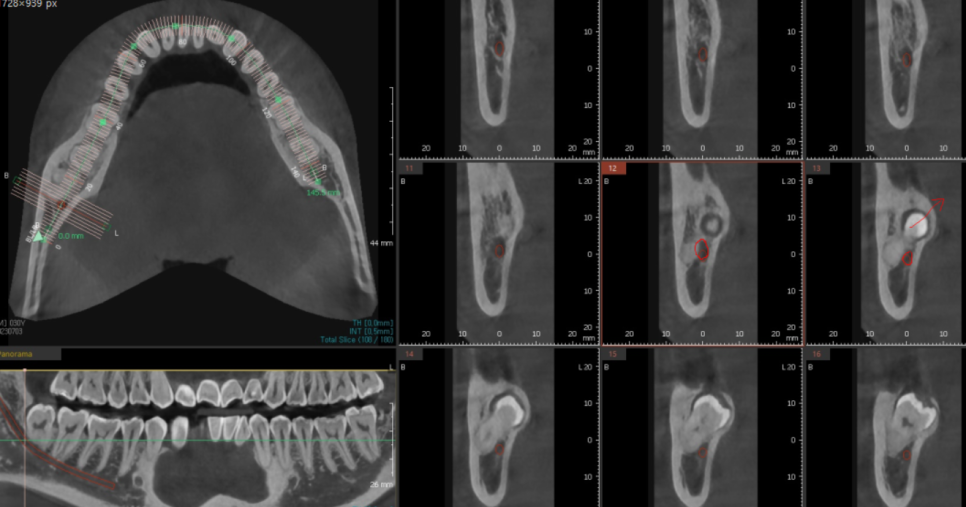

X-RAY부터 찍어보았는데요

아래 사랑니의 최대의 적

하치조 신경관과 딱! 붙어있네요.

자세한 것은 CT를 한장 찍어보기로 하고

3D-CT를 통해 사랑니와 신경이 근접해 있는 정도

어떻게 발치할 것인가

직접 그리면서 보여드렸죠.

화살표 방향으로 뽑아낼꺼다...

저희 계획중 일부입니다.